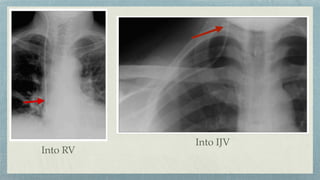

Into IJV

Into RV

Arterial puncture Via ASD into LA In azygous vein